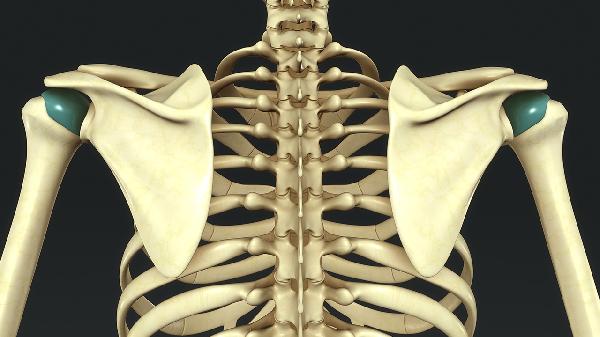

先天性胸廓畸形的严重程度因类型和个体差异而异,主要涉及漏斗胸、鸡胸、胸骨裂三类,需结合心肺功能评估、外观影响、并发症风险、治疗时机和长期预后综合判断。

漏斗胸可能导致心脏受压,严重时需3岁后手术矫正;鸡胸多影响外观,少数需胸骨矫形术;胸骨裂罕见但可能危及生命,需新生儿期紧急手术。Nuss手术、Ravitch手术和胸骨翻转术是常见术式。